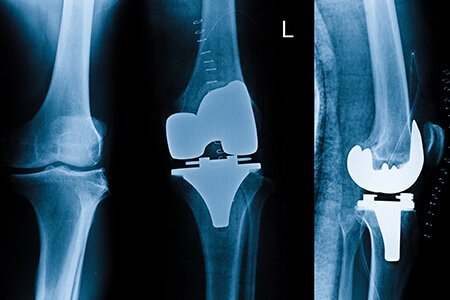

While many patients can be managed with the help of medicines, physical therapy or injections, some do not get any relief with these treatments. In such patients with advanced condition, knee replacement surgery, also called knee arthroplasty, is suggested. In this surgery, weight-bearing portion of the knee joint is replaced by an artificial structure. Today, knee replacement surgery is one of the most common bone surgeries performed around the world.